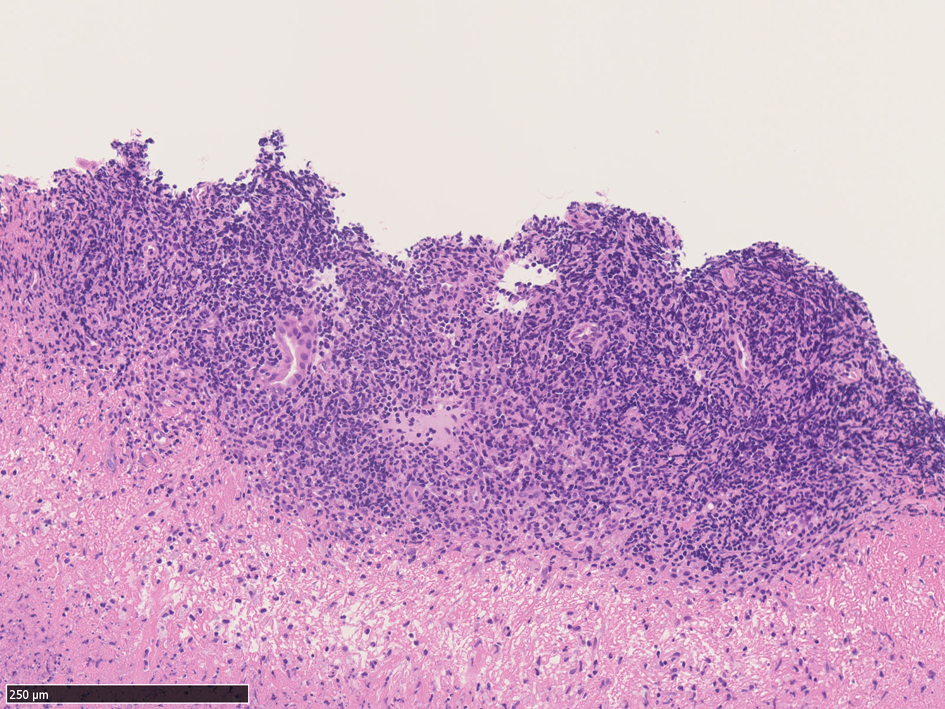

extranodal natural killer/ T-cell lymphoma, nasal type

鼻, 副鼻腔領域より採取された組織が, 壊死の強い炎症性肉芽組織の場合, 浸潤細胞にリンパ球が含まれていれば絶対CD56は染めておくようにしたい

鼻・副鼻腔の壊死組織では extranodal natural killer/T-cell lymphoma, nasal typeを見落とさないことが大事 浸潤しているリンパ球は小型リンパ球で異型の見られないことが多い.

IWT case 64year-old female

左から鼻腔より採取された壊死組織断片。真菌の増殖がある。よく見ると腺周囲に小型の異型所見に乏しいリンパ球が密に浸潤している。念のためCD56を染めると多くのリンパ球が陽性を示しNK/T-cellの浸潤増殖の可能性がでてきた。EBER-ISHではB細胞に陽性となっている所見。以上からNK/T-cell lymphoma nasal typeの壊死病変を採取したことが強く疑われ臨床科に連絡して精査, 再度確定診断をおこなうようになった。

3.小型低異型度型--->組織像図3 小型で低異型度のリンパ球がびまん性に浸潤. 慢性炎症との鑑別が難しい. 上記の症例.

診断はCD3+(細胞質+, 表面-; FCMの抗体ではsCD3は陰性となる), CD56+, CD5-, cytotoxic molecule[granzymeB, TIA-1, perforin,etc]を染色, EBER-ISHでEBVの存在を確認する.